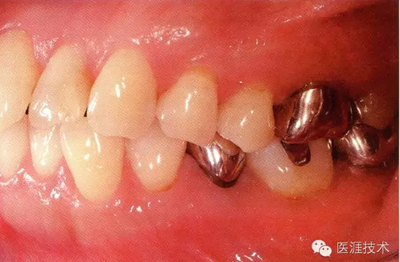

56歲牙周炎男性的臨床照片

正在服用高血壓藥中的56歲男性。菌斑控制得不好。通過牙周探診,全頜有4~6mm的牙周袋,在X光片中可以看到全頜中度牙槽骨吸收,磨牙處一個地方是重度牙槽骨吸收。通過比較牙周病進(jìn)展?fàn)顟B(tài),邊緣部有大范圍浮腫(發(fā)紅、腫脹),和纖維性肥厚。這也可能是服用中的降壓藥的副作用導(dǎo)致的。因?yàn)檠例l、牙槽骨比較厚,牙齦呈架子狀。